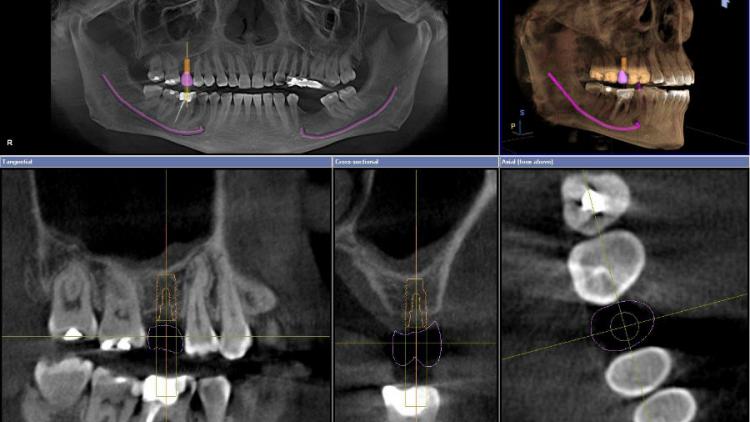

3D снимок зубов (компьютерная томография)

Трехмерная модель зубочелюстной системы, которая позволяет очень точно определить состояние зубов, размер и плотность кости, провести любые необходимые измерения. Данный вид исследования необходим как при сложном эндодонтическом лечении, так и при имплантации.

Делается на компьютерном томографе.